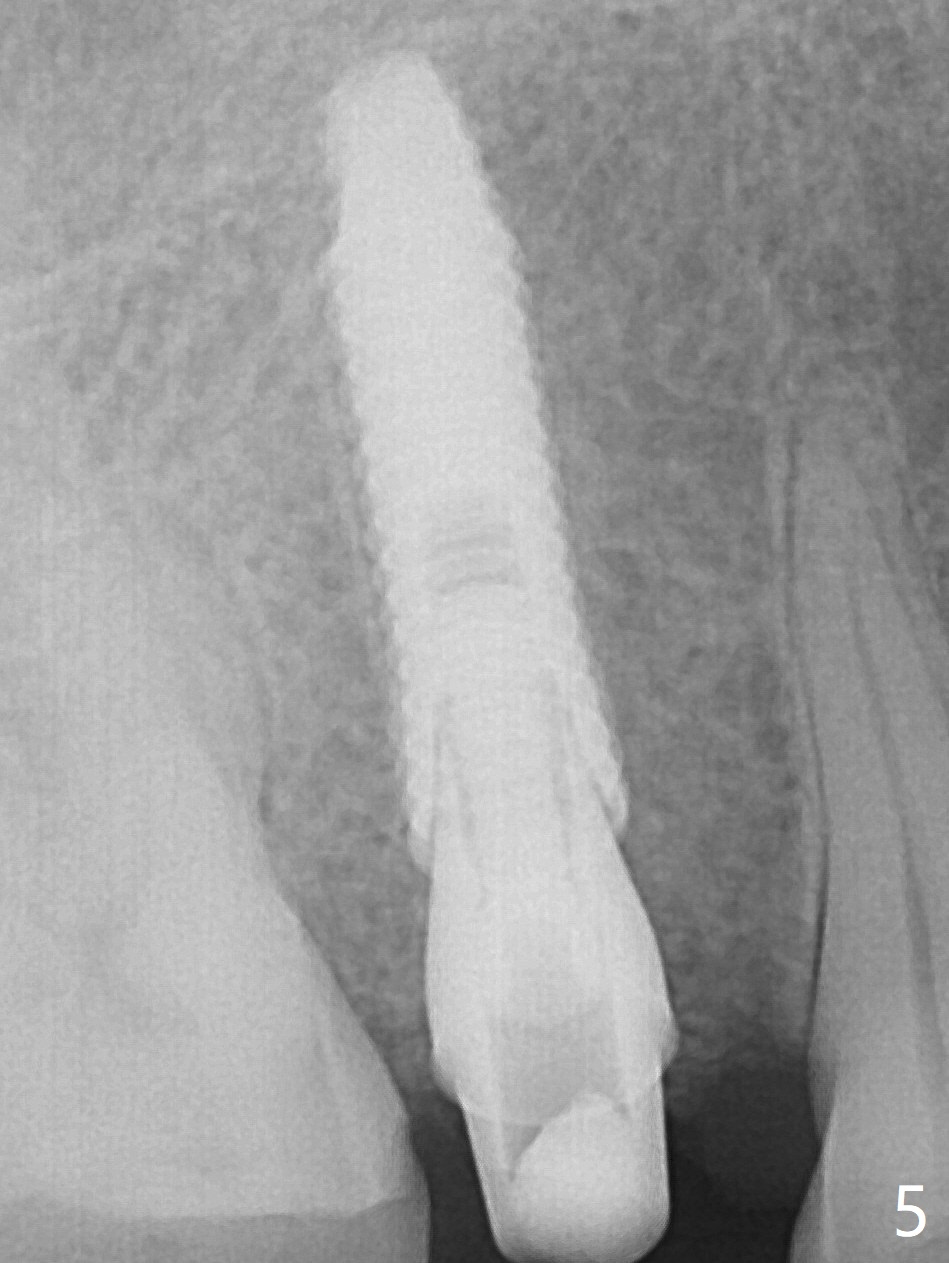

A 61-year-old man cracks the tooth #4 while chewing on a piece of chicken bone (Fig.1,2). Initial osteotomy appears to be able to hold a 16 mm long implant (Fig.3). After sequential osteotomy, a 4x16 mm implant is initially unable to be seated low enough for the buccal crest. Following packing the osteotomy with Vanilla Graft (.5-1 mm) and additional 2-3 mm depth of osteotomy, the implant is placed slightly apical to the buccal crest (Fig.4,5); with placement of Vanilla Graft (*) and a 4.5x4(4) mm abutment, an immediate provisional is fabricated to close the socket. The provisional is removed 3 months postop because of poor local oral hygiene (Fig.6,7). The gingiva is healthy 2-3 weeks later; it is easy to take impression (Fig.8).